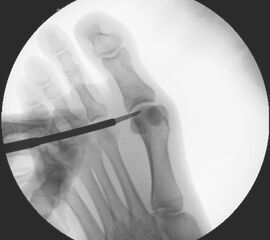

Zum Lesen der Bildbeschreibung und zur Vollansicht bitte die Bilder anklicken.

• Positionierung des Bildwandlers: 90° Winkel zum Os metatarsale I. Benötigt wird die Durchleuchtung des Vorfußes a.p., seitlich und schräg.

Operationstechnik

Der von Isham/Reverdin beschriebenen minimal invasiven Technik zur Korrektur einer Hallux valgus Deformität liegen 4 Operationsschritte zu Grunde:

1. Abtragung der Exostose am Köpfchen des 1. Mittelfußknochens

2. Subcapitale intraartikuläre Osteotomie

3. Laterales Release

4. Akin Osteotomie der Großzehengrundphalanx

Die Folge der Operationsschritte sollte strikt von 1. - 4. erfolgen, da ansonsten die mediale Closing Wedge Osteotomie bei vorzeitigem lateralem Release und/oder Akin Osteotomie nicht geschlossen werden kann. Nach der von Isham beschriebenen Originaltechnik finden Implantate keine Anwendung, zur Sicherung und besseren Fixation können osteosynthetische Verfahren angewandt werden (siehe auch Fehler, Gefahren und Komplikationen).